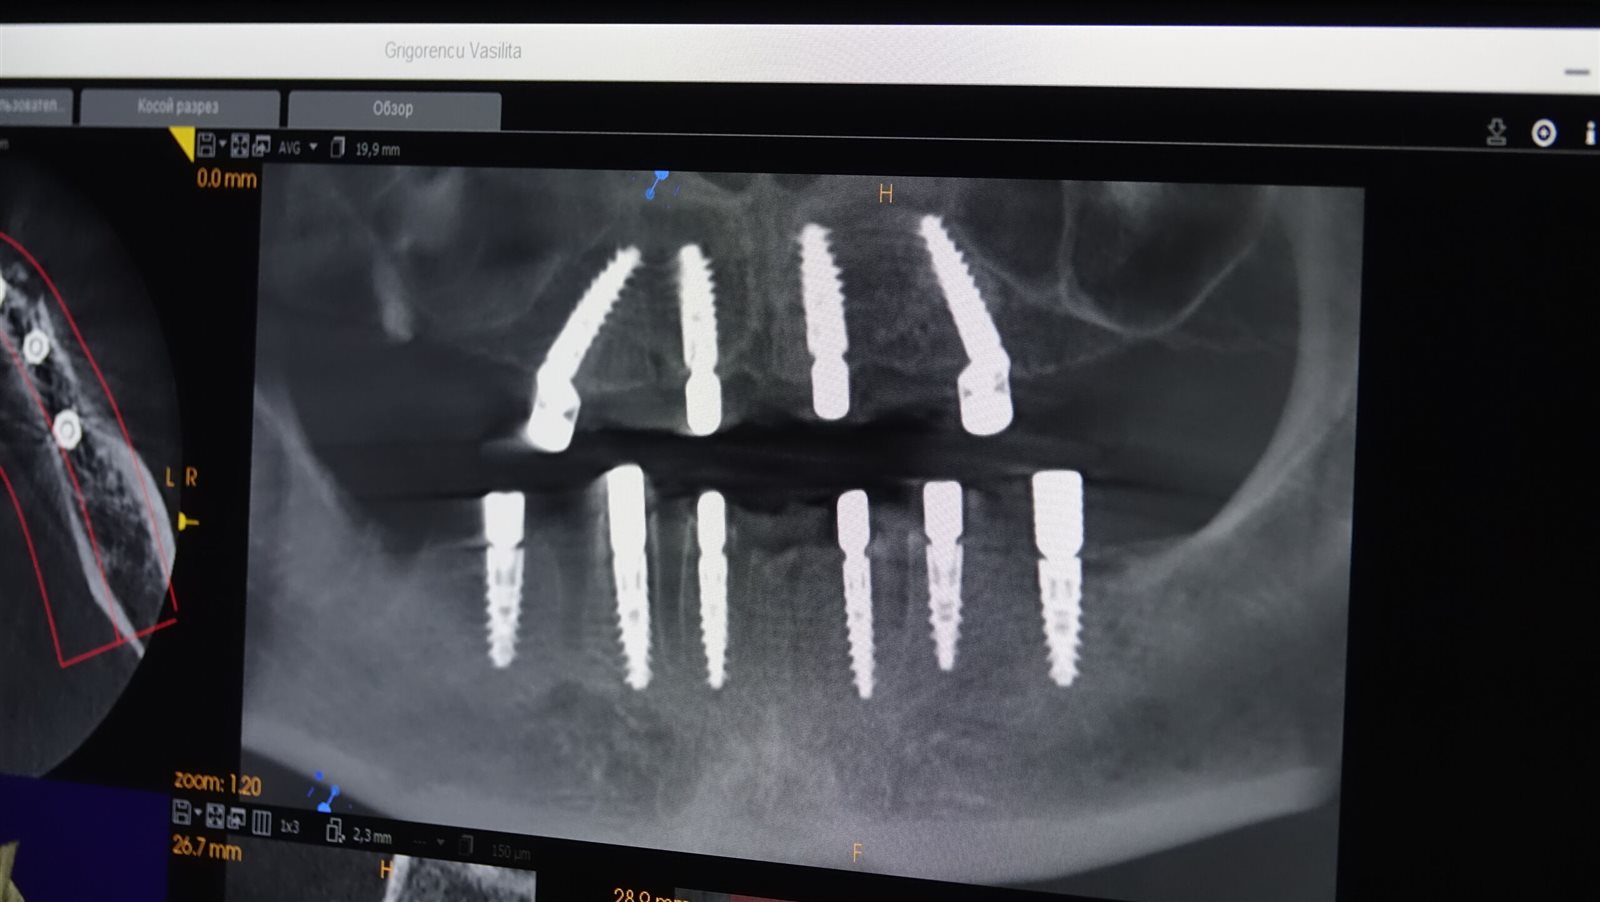

وذكر الدكتور باسم نبيل الفحل، أن طب الأسنان الرقمي يساعد على التخطيط للحالة قبل بدء الزراعة بمجرد عمل أشعة ثلاثية الأبعاد واستخدام مادة طابعة للفكين يتمكن الطبيب من تحديد الشكل المستقبلي للأسنان، وبعد ذلك يتم إدخال الأشعة للكمبيوتر لحساب موقع إطباق الأسنان ومستواه وشكل الأسنان خاصة حال كان المريض فاقد عدد كبير من الأسنان، وبالتالي لديه مشكلة أساسية، وهي عدم وجود أسنان وضمور اللثة بعد الخلع، ولذلك يحتاج الطبيب إلى تعويض شكل اللثة وجعل الابتسامة طبيعية.

وأضاف أن عمل غرسات للزراعة باستخدام الأشعة التي يجلبها المريض تساعد أن تكون الغرسة مناسبة له ويتم وضعها على الكمبيوتر حتى تكون مدروسة بشكل كامل، وفي بعض الحالات يتم إجراء طباعة ثلاثية الأبعاد لعظام الفكين للاختيار الدقيقة للغرسات لتأكد من حصول المريض على أفضل نتيجة.